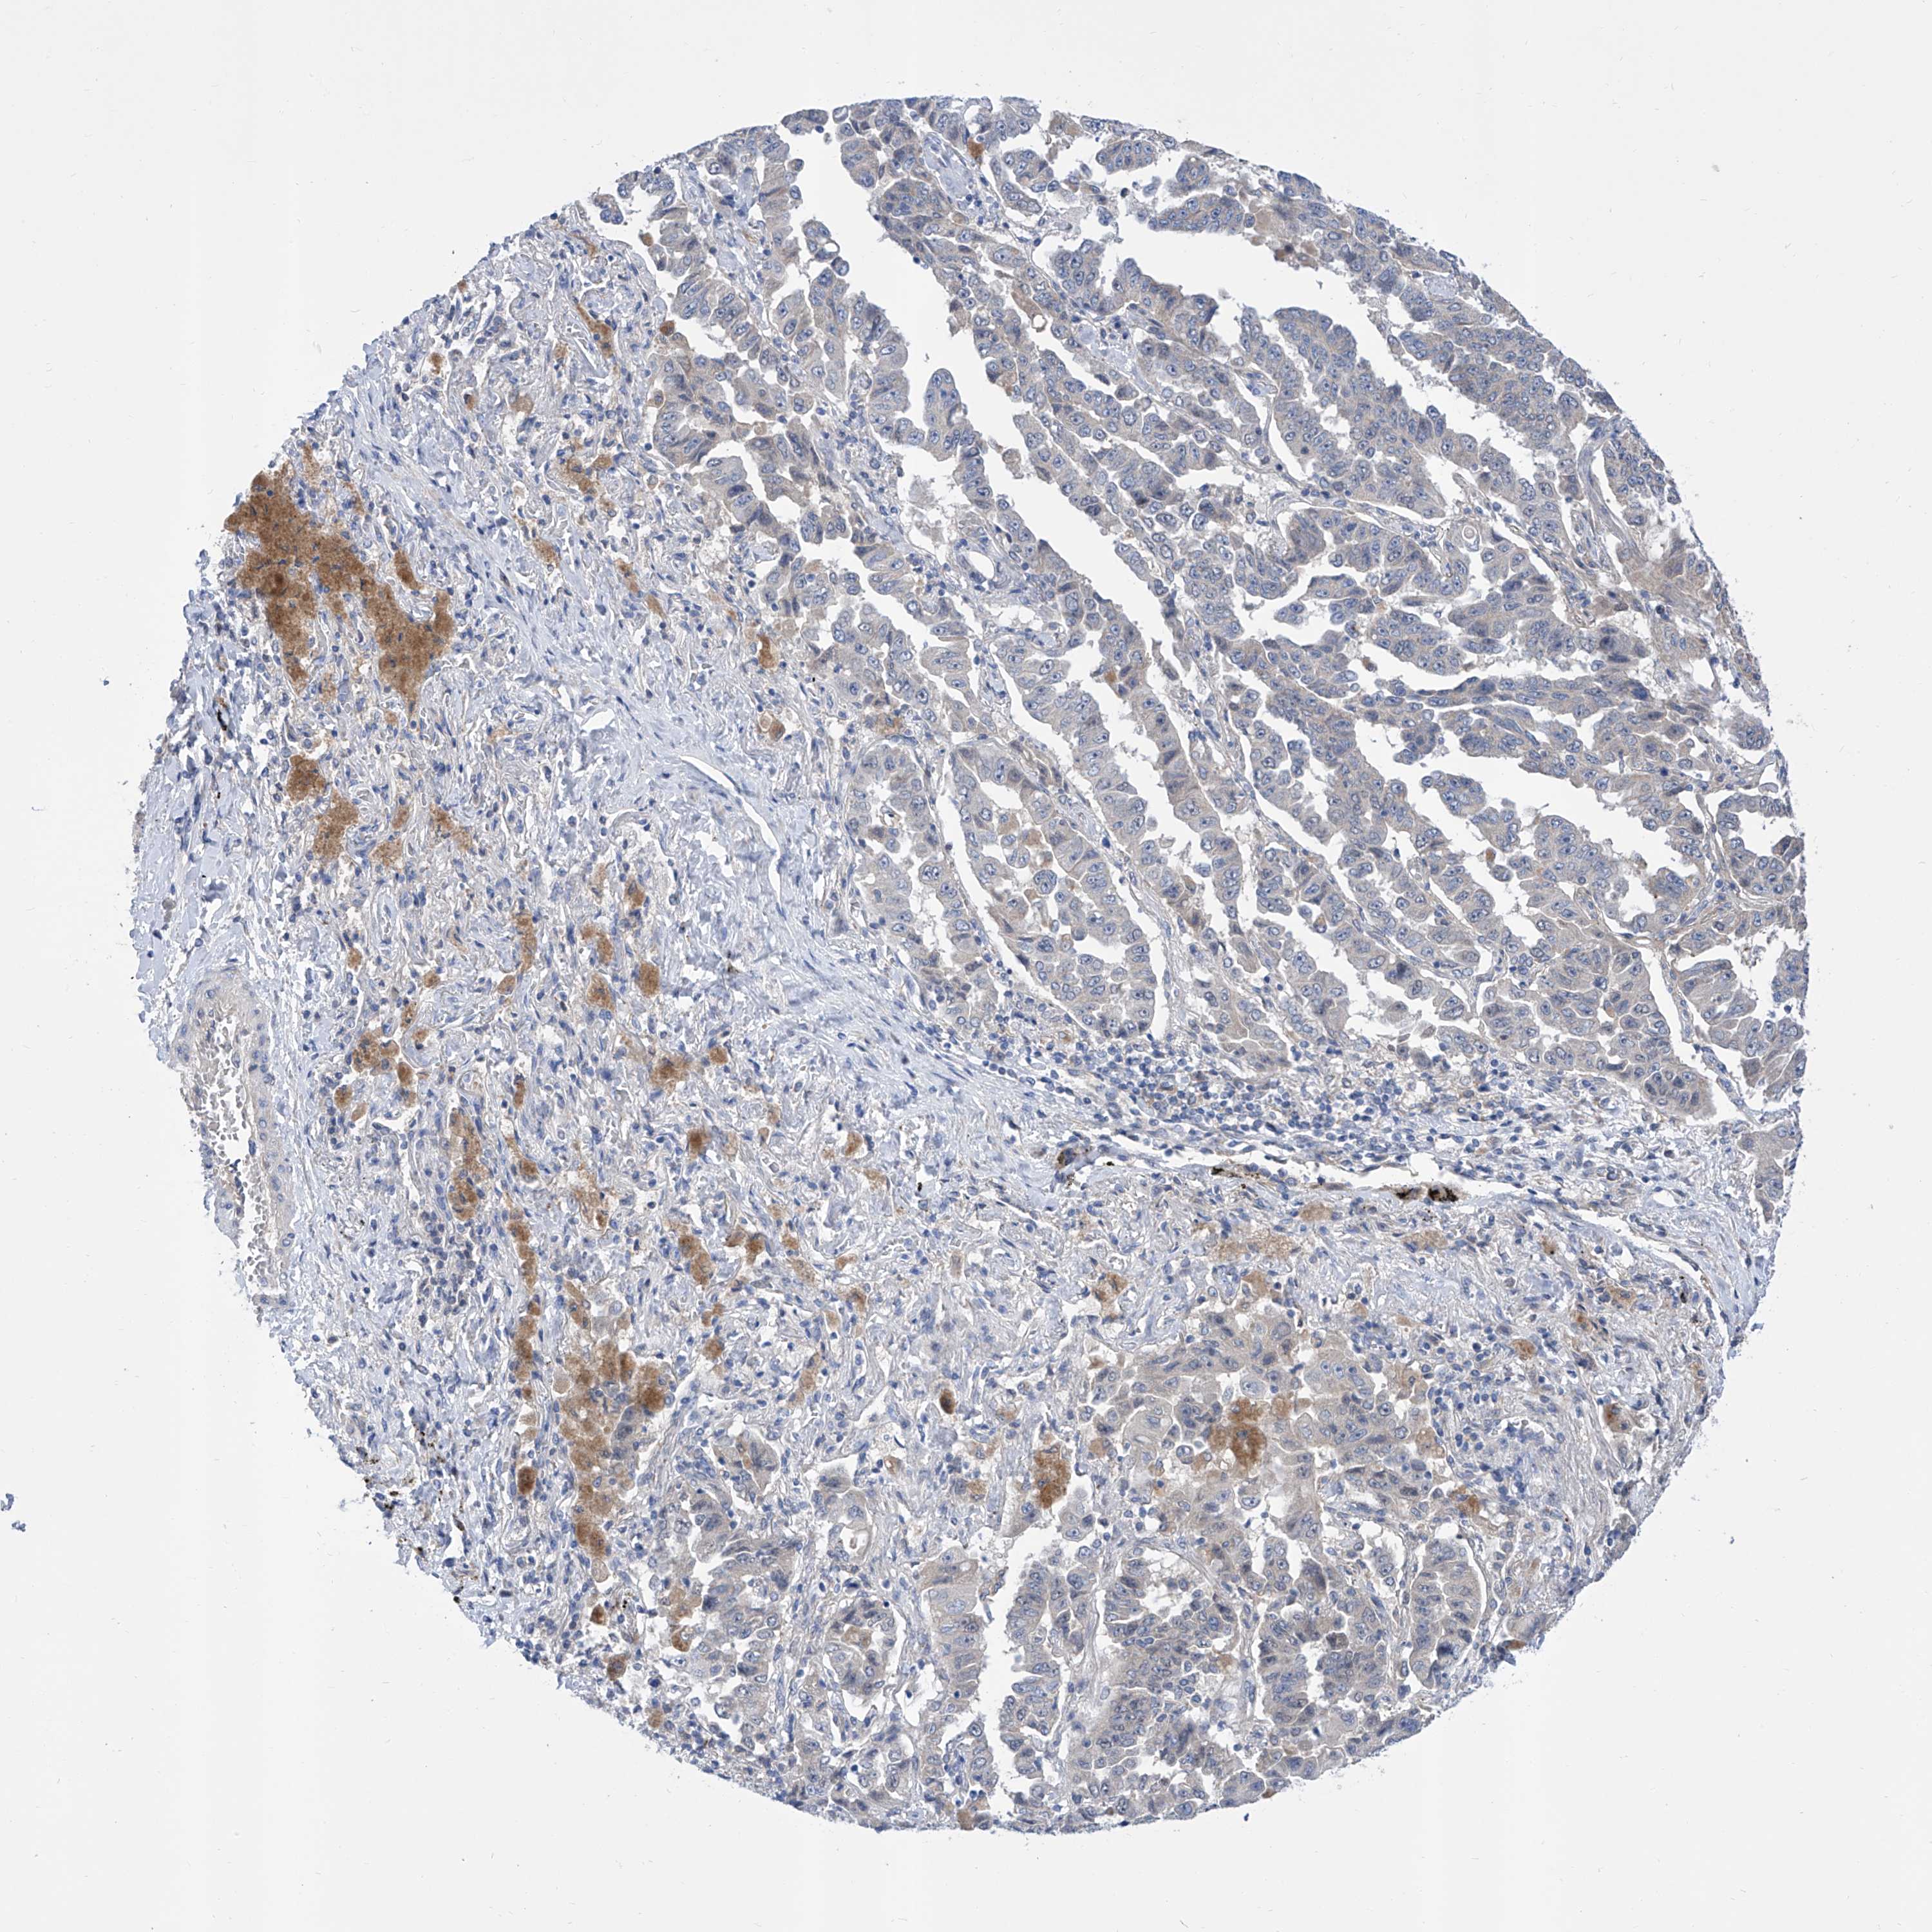

CANCER LUNG CANCER Show tissue menu

LUAD TCGA LUAD VALIDATION LUSC TCGA LUSC VALIDATION PROTEIN LUAD CPTAC PROTEIN LUSC CPTAC PROTEIN EXPRESSION

ANTIBODIES

AND

VALIDATION